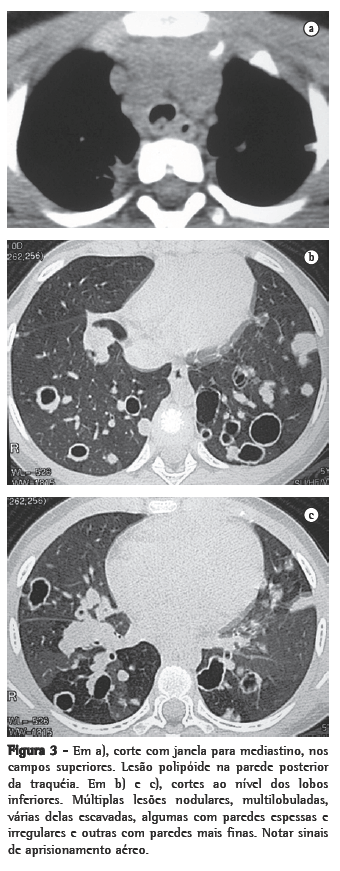

ResultadosNos 8 casos foram observadas na TC formações polipóides na traquéia. Em 1 deles, identificou-se também uma lesão em brônquio principal. Sete pacientes mostravam comprometimento do parênquima pulmonar. Em todos foram observadas lesões nodulares escavadas, com contornos internos irregulares, e paredes de espessuras variadas, com aspecto multilobulado em 6 casos, e com confluência das lesões em 5 deles (Figuras 1 a 5). Nódulos sólidos foram vistos em 6 pacientes, Em apenas 1 dos casos foram vistos níveis líquidos. As lesões predominaram nas bases em 3 pacientes, nos terços médios em 2, e em 2 não havia predomínio de distribuição. Em 1 dos pacientes, foi observada associação com massa, e em outro, com consolidação. Neste último paciente (Figura 5) foi constatada degeneração maligna em múltiplas lesões. Sinais de aprisionamento aéreo também foram observados em 1 caso. Em nenhum deles detectou-se linfonodomegalia ou derrame pleural.

A TC, particularmente com aquisição volumétrica (espiral), é superior às radiografias de tórax no reconhecimento de nódulos ainda pequenos, nas fases iniciais de disseminação pulmonar, por sua melhor caracterização e visualização de vegetações nodulares traqueobrônquicas. Os achados tomográficos incluem estreitamento nodular, focal ou difuso, da via aérea. Os nódulos crescem na superfície mucosa, e sua extensão intraluminar é melhor avaliada por TC.(3) São alterações facilmente correlacionadas à doença quando se dispõe da história clínica de papilomatose.(4) Outros achados relacionados à obstrução das vias aéreas e/ou infecções associadas são atelectasias, consolidações, aprisionamento aéreo e bronquiectasias.(2-4) Na nossa casuística, formações polipóides na traquéia foram observadas em todos os exames tomográficos. Sete pacientes mostravam comprometimento do parênquima pulmonar, caracterizado por lesões nodulares escavadas, com contornos internos irregulares, e paredes de espessuras variadas, com aspecto multilobulado e tendendo à confluência. Nódulos sólidos foram vistos em 6 pacientes. Em nenhum deles detectou-se linfonodomegalia ou derrame pleural.